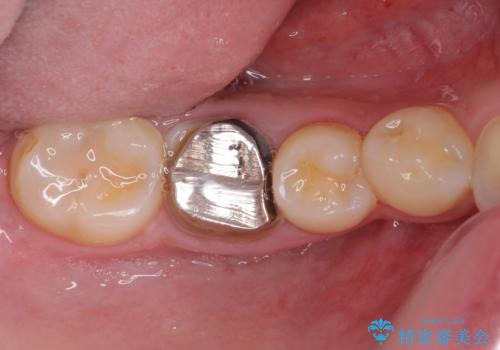

- 放置した虫歯や抜いたままの奥歯、前歯のデコボコを気にして来院された患者様です。

矯正治療を行う前に、根管治療の必要な上顎前歯と下顎大臼歯の根管治療を行い、矯正治療の途中で下顎の欠損部にインプラント埋入することとし、矯正治療後に補綴治療を行うこととしました。